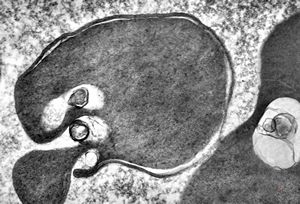

M,33y. | blood - hairy cell leukemia- ribosome-lamella complexin tricholeukocyte

M,41y. | hairy cell leukemia - spleen - ribosome-lamella complex in tricholeukocyte